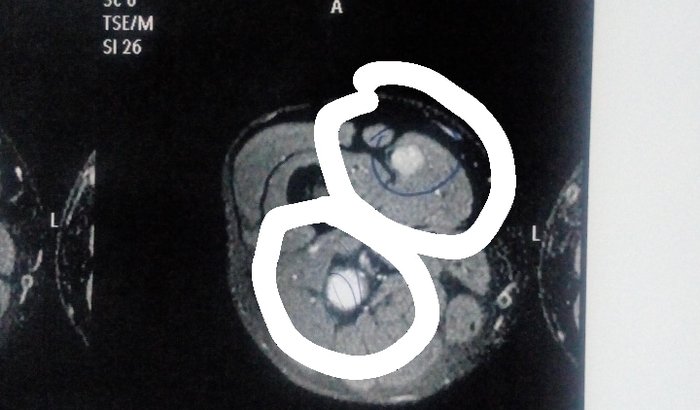

A algum tempo atrás meu pai comecoca sentir pequenas dores na perna dando pontada ate os seus pés, não conseguia mais dirigir muito e nem caminhar muito, que ao chegar a noite comecava a dar fortes pontadas e ele não dormia de dor, com o aumento das dores ele começou a procurar o medico para descobrir do que se tratava as dores, fez várias ressonâncias mas não diagnosticava nada nas pernas porém, diagnósticou que tinha problema na coluna ele começou a tratar mas não adiantou, as dores na perna ainda continuavam, então ele resolveu ir e fazer uma ressonância só no local da perna onde tinha a dor e diagnosticou que tem 2 tumores em sua coxa, 1 em cima e o outro no nervo ciático de baixo do joelho se essa cirurgia não for feita logo meu pai poderá correr perigo de afetar sua perna toda e acontecer o pior. Então eu venho pedir que quem puder nos ajudar com as doações ficaremos muito gratos do fundo do coração!